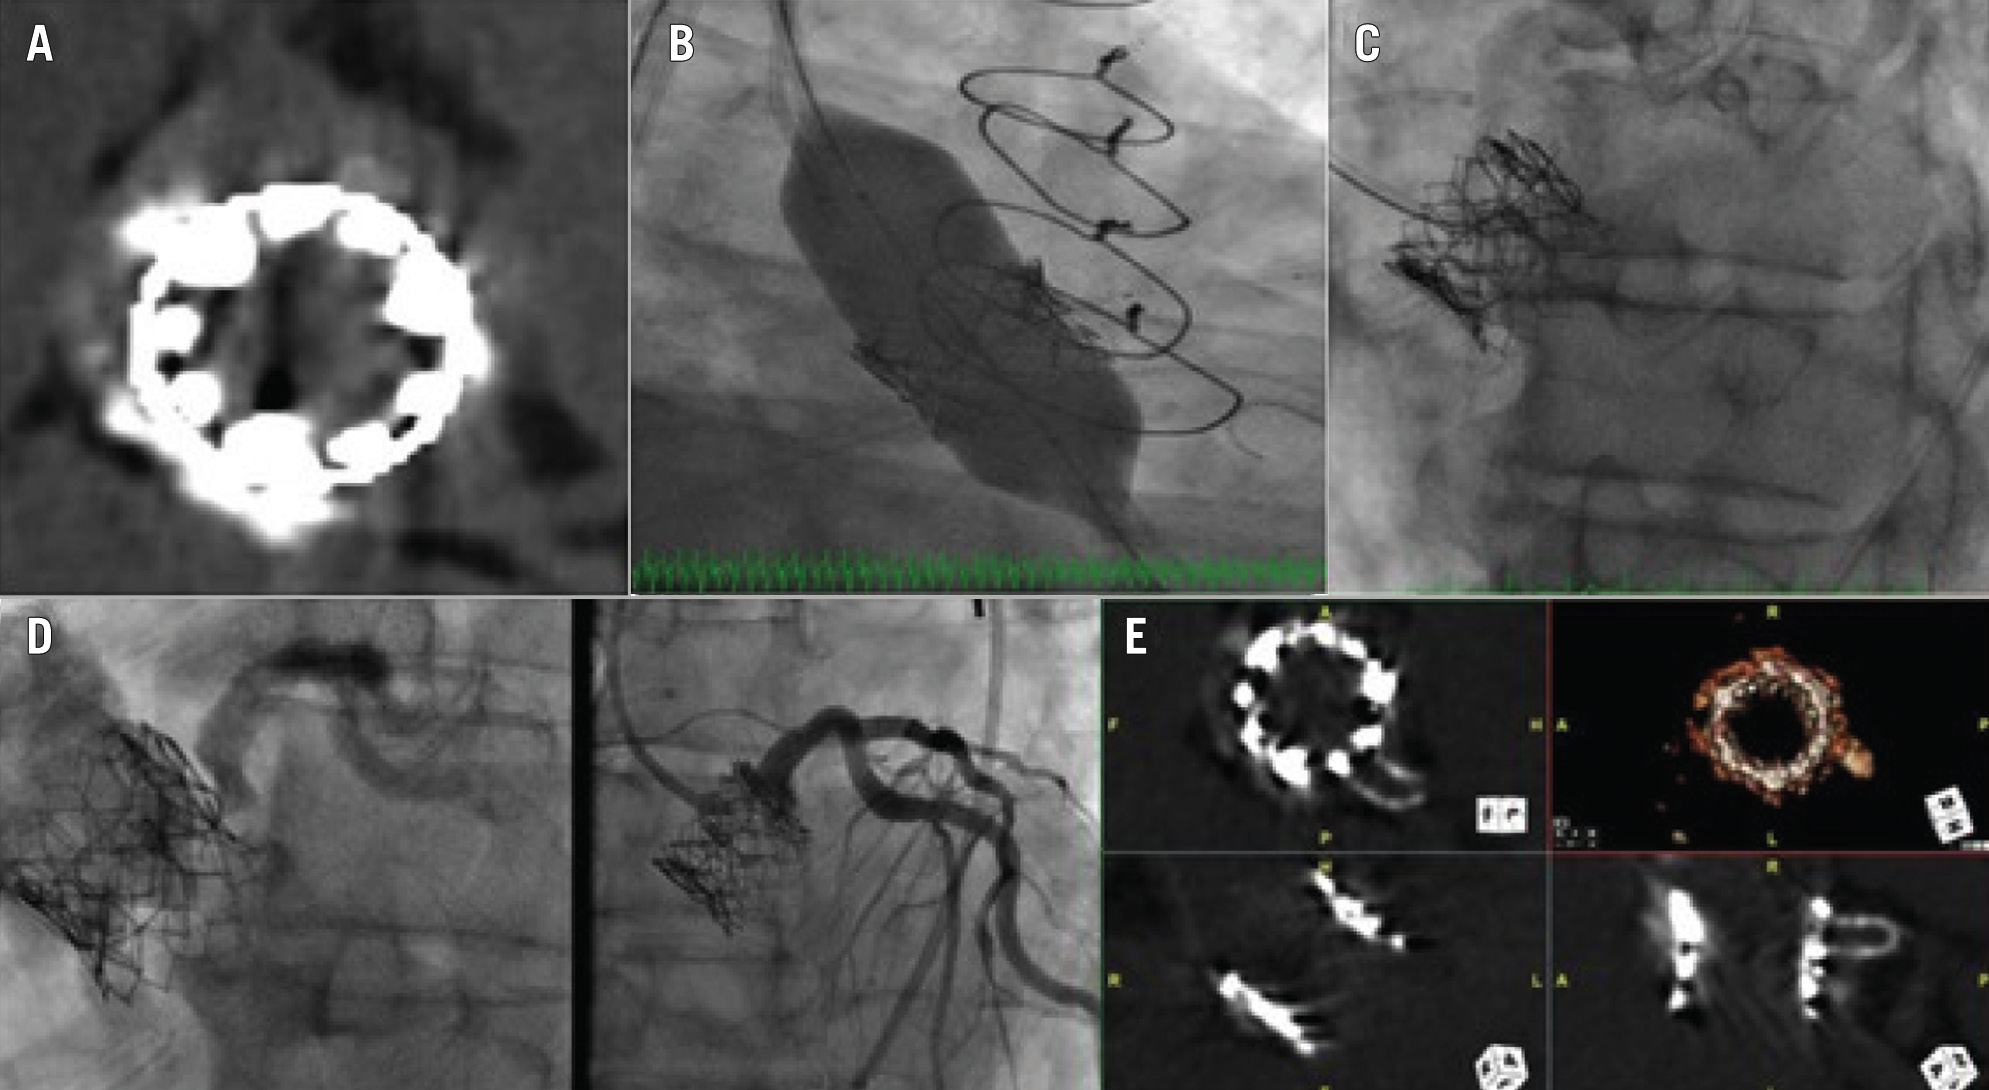

A third strategy is the Bioprosthetic Aortic Scallop Intentional Laceration to prevent Iatrogenic Coronary Artery obstruction (BASILICA) technique to split either native or bioprosthetic aortic valve leaflets prior to TAVI in order to maintain blood flow into the coronary sinus. The procedure involves intentional laceration of the leaflets using radiofrequency energy delivered to a guidewire suspended between two guiding catheters7879. In the BASILICA trial78, the procedure was successful in 28/30 subjects, and there was 100% freedom from coronary occlusion during TAVI. The key advantage of the BASILICA procedure is the possibility of avoiding stent implantation, which mitigates the need for prolonged DAPT therapy and avoids potential stent-related complications such as underexpansion or restenosis. Typical BASILICA for redo-TAVI has not been proven to be effective, and use of a balloon-assisted (BA-BASILICA) technique is recommended. We have previously reported a novel electrosurgical bailout technique for acute left main occlusion following redo-TAVI in a surgical bioprosthesis (Figure 7)80. Dedicated devices for leaflet splitting to prevent coronary obstruction have been developed and are under investigation81.

Figure 7. Treatment of a 79-year-old male who presented with critical aortic stenosis and had a history of CKD, SAVR and CABG (LIMA-LAD), redo-SAVR, PCI to LAD for LIMA graft failure, and valve-in-valve TAVI with a 23 mm SAPIEN XT for surgical bioprosthetic dysfunction. Coronary angiography showed patent stents. Non-contrast CT showed an LM height of 10 mm and a virtual transcatheter valve-to-coronary distance of 4 mm. The valve-to-aorta distance was 18 mm. Given the high likelihood of coronary obstruction, we preplanned the use of an electrosurgical bailout technique to recanalise the LM coronary artery. A) SAPIEN XT valve (Edwards Lifesciences) commissural alignment after valve-in-valve TAVI at 3 o’clock, 6 o’clock, and 10 o’clock. B) Transfemoral redo-TAVI was performed using a 23 mm SAPIEN S3 Ultra (Edwards Lifesciences). The LM was protected using a 6 Fr Amplatz Left 1 guide, guide extension catheter, coronary guidewire, and semicompliant coronary balloon in the LAD. C) Nearly 15 minutes after groin closure/haemostasis, the patient started complaining of severe chest pain with no ischaemic changes on ECG and normal left ventricular function on TTE. A non-selective angiogram demonstrated severe eccentric stenosis of the LM. A 7 Fr Judkins Left 4 guide was placed via the left femoral artery in the middle of the left sinus. An Astato XS 20 wire (Asahi Intecc) with a PiggyBack Wire Converter (Teleflex) was placed at the tip of the guide. Using electrosurgery at 70 W to perform a cut, the SAPIEN XT and surgical valve leaflets were punctured while injecting 5% dextrose. D) The patient was administered aspirin 325 mg and clopidogrel 600 mg orally. A 4×16 mm drug-eluting stent was proximally placed 1 mm outside the SAPIEN XT leaflet, as identified on intravascular ultrasound, at 14 atmospheres, and postdilatated with a 5.5×8 mm non-compliant balloon at 20 atmospheres. The final angiogram showed TIMI 3 flow in the LM and no residual stenosis. E) A non-contrast CT demonstrated fortuitous commissural alignment of the S3 Ultra posts with the SAPIEN XT posts. CABG: coronary artery bypass grafting; CKD: chronic kidney disease; CT: computed tomography; ECG: electrocardiogram; LAD: left anterior descending artery; LIMA: left internal mammary artery; LM: left main; PCI: percutaneous coronary intervention; SAVR: surgical aortic valve replacement; TAVI: transcatheter aortic valve implantation; TIMI: Thrombolysis in Myocardial Infarction; TTE: transthoracic echocardiogram